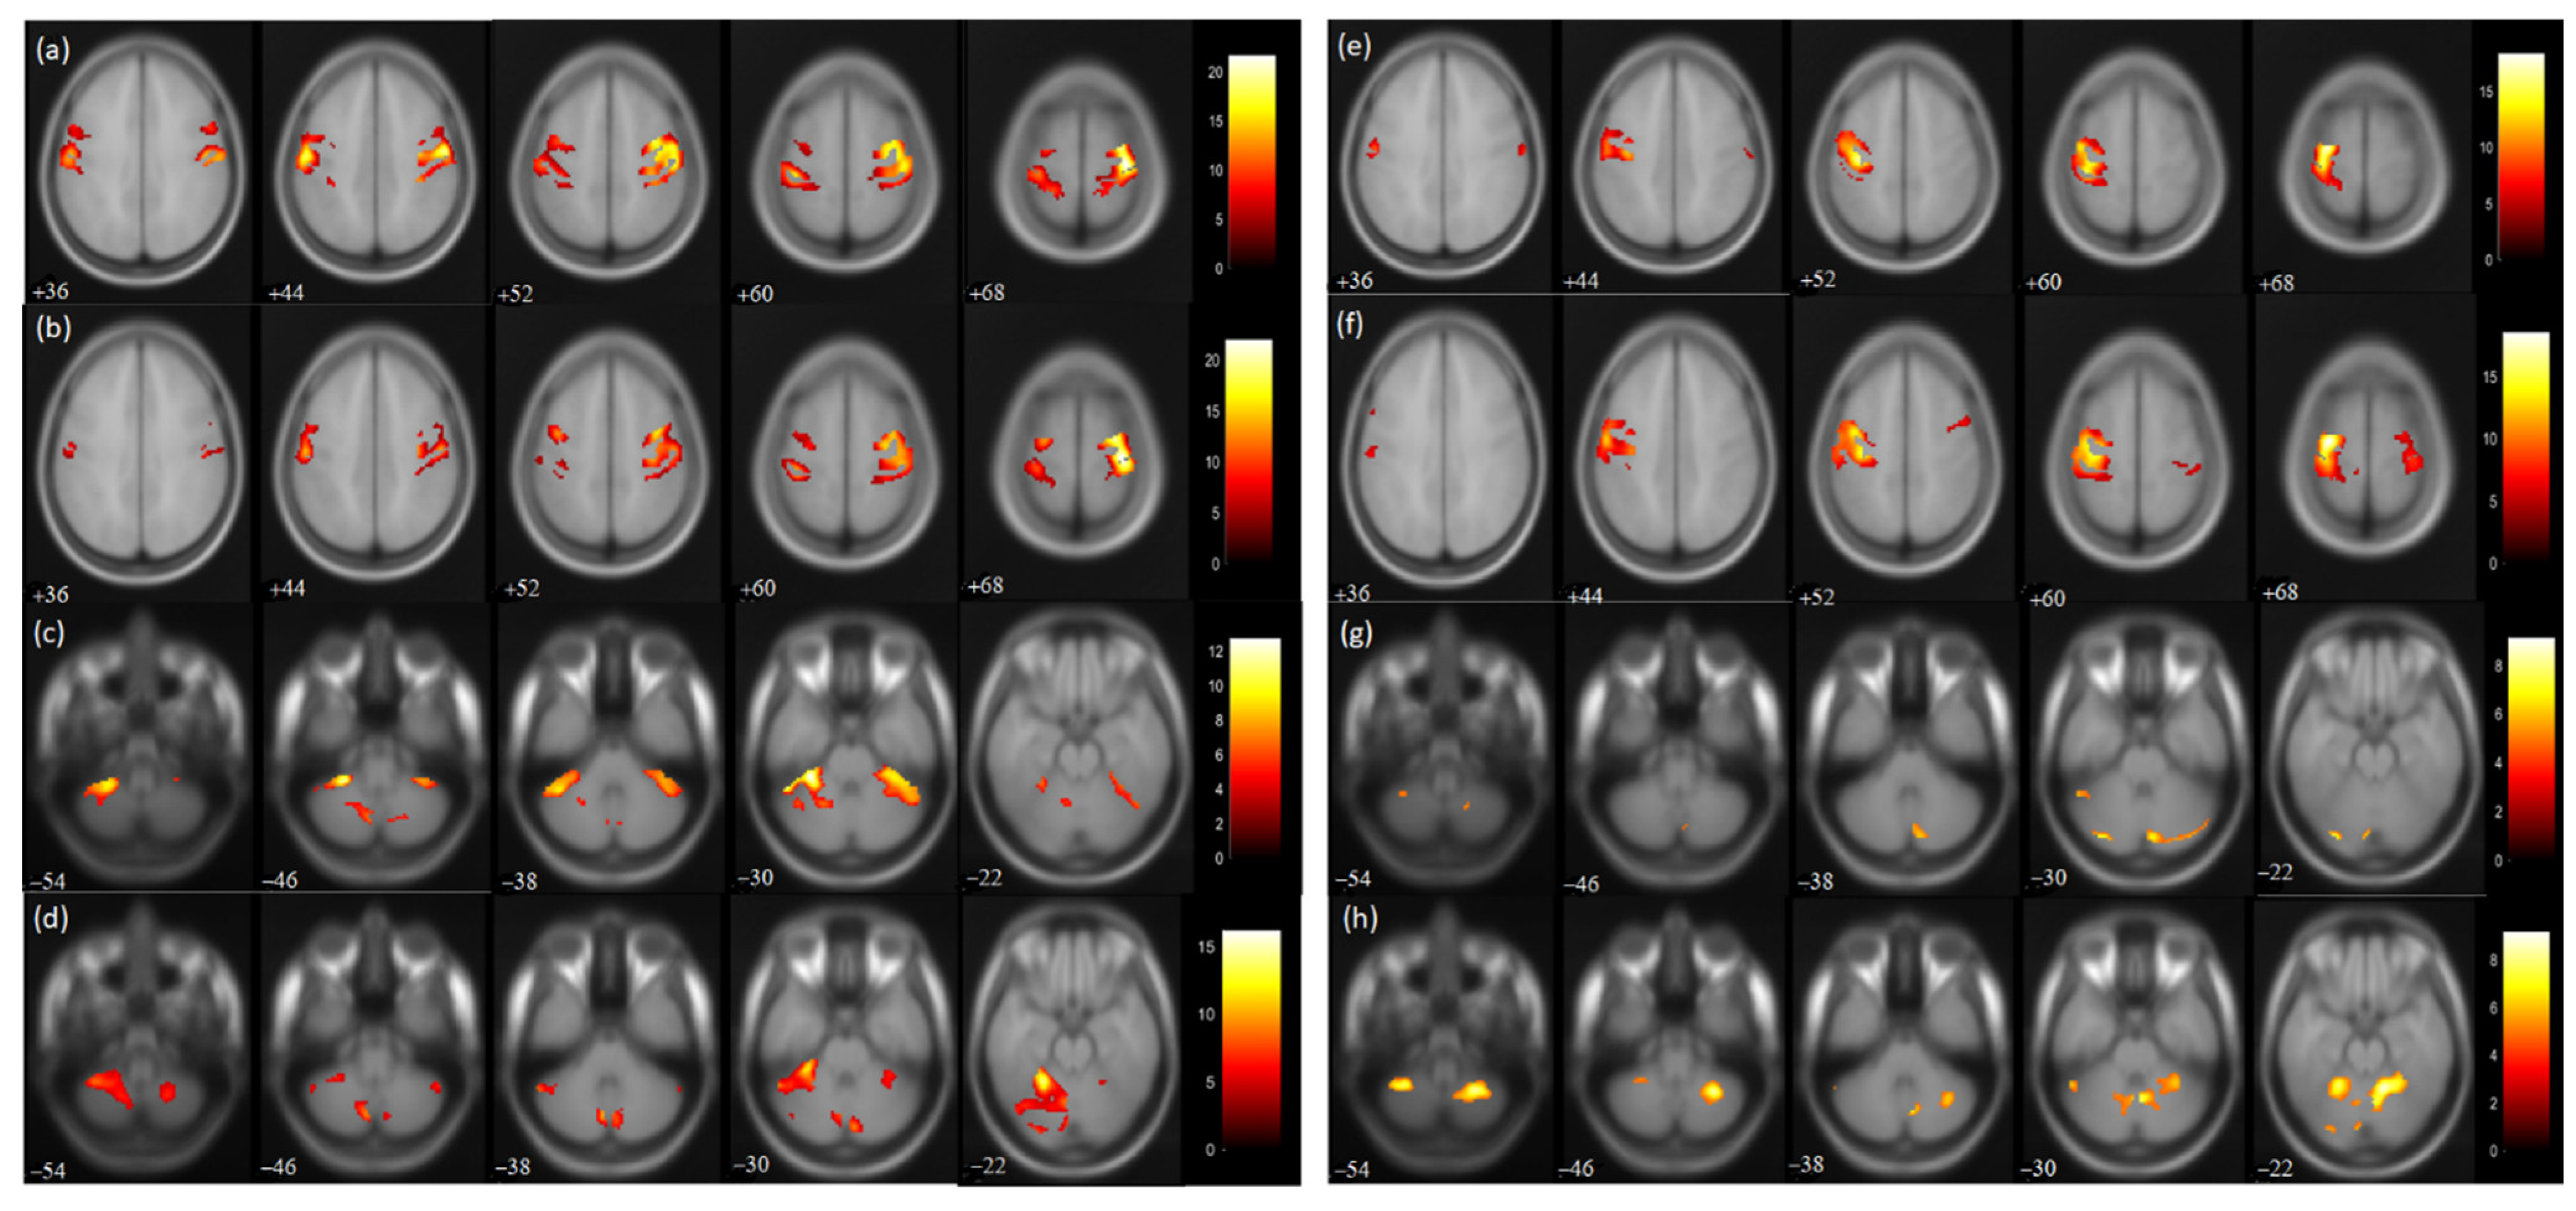

3.3. fMRI measures

| P: Task by Affected Hand | ||||||||||

|---|---|---|---|---|---|---|---|---|---|---|

| Region | PRE | POST | ||||||||

| No. of Voxels | Threshold | No. of Voxels | Threshold | LI/IpsCB Ratio | No. of Voxels | Threshold | No. of Voxels | Threshold | LI/IpsCB Ratio | |

| Hemisphere | Right | Left | Right | Left | ||||||

| PrG | 1695 | 21.66 | 946 | 17.43 | 0.28 | 1248 | 22.01 | 619 | 13.75 | 0.33 |

| PoG | 1549 | 19.68 | 1349 | 19.07 | 0.07 | 1159 | 21.23 | 619 | 13.75 | 0.303 |

| CBM Exterior | 980 | 9.66 | 1296 | 12.73 | 0.56 | 203 | 9.84 | 2094 | 16.17 | 0.911 |

| SMA | 703 | 14.48 | 619 | 15.2 | 0.06 | 301 | 14.79 | 245 | 12.36 | 0.102 |

| P: Task by Unaffected Hand | ||||||||||

| PrG | 18 | 5.59 | 1362 | 18.35 | 0.97 | 77 | 7.7 | 1428 | 18.56 | 0.89 |

| PoG | 73 | 8.02 | 808 | 15.21 | 0.834 | 208 | 8.12 | 1106 | 14.22 | 0.68 |

| CBM Exterior | 271 | 8.24 | 72 | 9.11 | 0.79 | 443 | 9.16 | 180. | 8.32 | 0.71 |

| SMA | 61 | 7.16 | 71 | 9.28 | −0.075 | 260 | 8.32 | 375 | 11.52 | −0.181 |